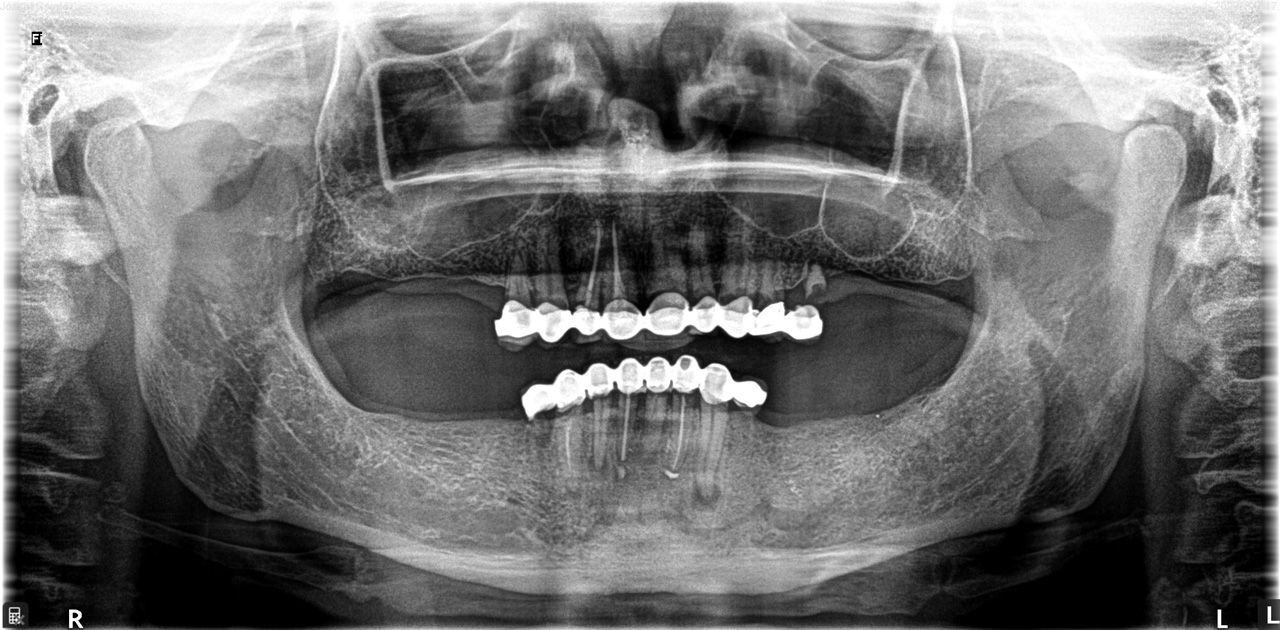

Alsó állcsont teljes rehabilitációja 72 óra alatt

Alsó állcsont teljes rehabilitációja 72 óra alatt, azonnal terhelhető implantátumokkal súlyos paradontitisben szenvedő dohányzó páciens esetében. Az alsó állcsont fogai mind mozogtak az előrehaladott fogágypusztulás miatt.

A fogakat eltávolítottuk, a gyulladt, fertőzött csontot kitakarítottuk, kifertőtlenítettük, majd azonnal implantáltunk.

Svájci, IHDE márkájú, azonnal terhelhető implantátumokat helyzetünk be, és ezekre harmadnapra rögzített, hosszútávú, fémvázas, esztétikus műanyaggal leplezett hidat ragasztottunk be.

Ezt az ideiglenes hidat a sebek gyógyulása miatt használjuk, de tartóssága miatt véglegesként is használható. A legtöbb esetben, ahogy itt is, 6 hónap múlva porcelán hídra cseréljük, a teljes gyógyulás után.